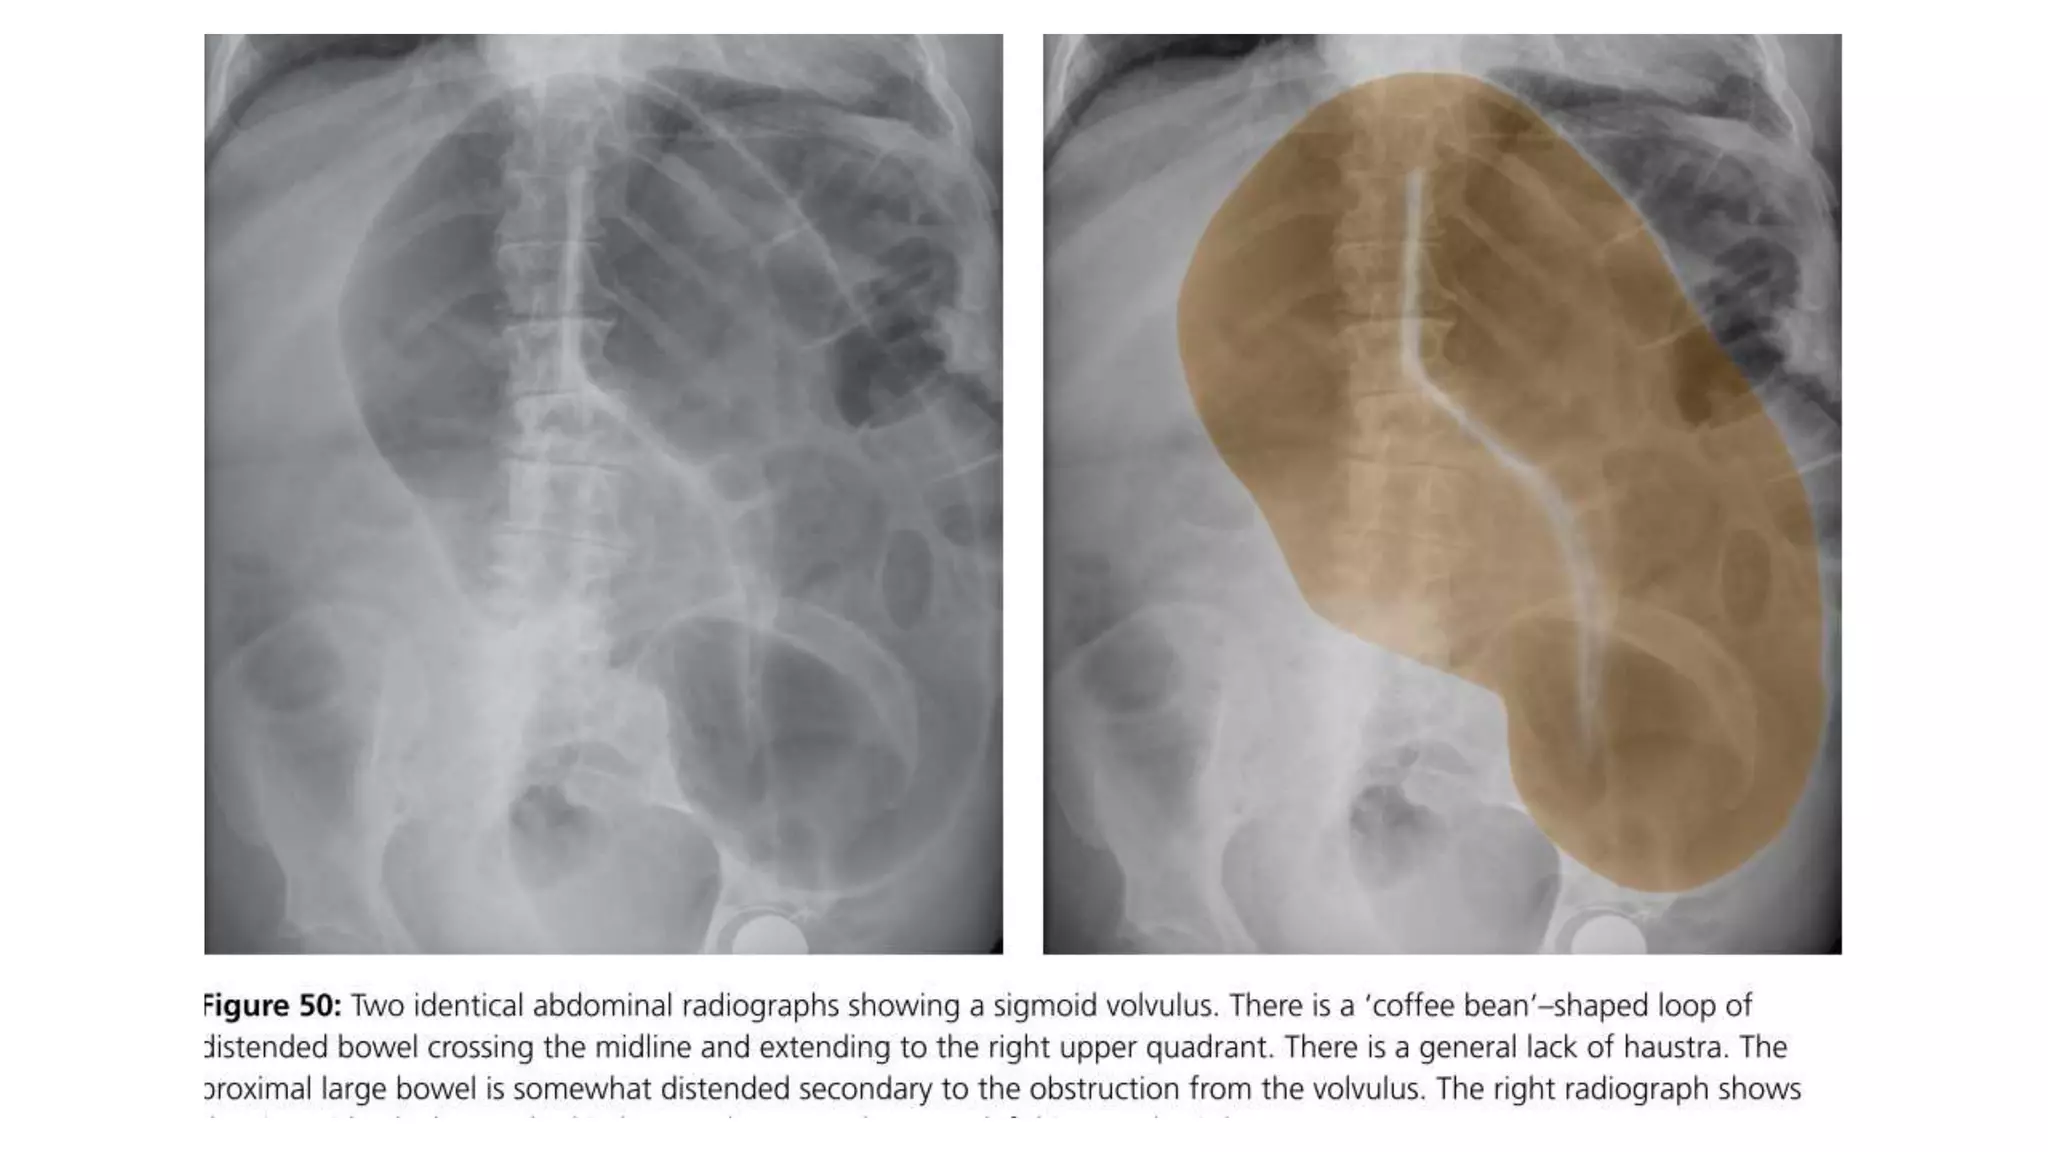

Radiological features in large bowel obstruction

• Colonic distension usually visualized in the periphery

• show the hustrations of the Taenia Coli.

• absence of rectal air and air fluid level if ileocecal valve incompetent

• May also demonstrate the cause of obstruction (volvulus)

Differentiate mechanical from pseudoobstruction

Define level and type of obstruction

volvulus bird beak appearance

Rectal cancer apple- core appearance